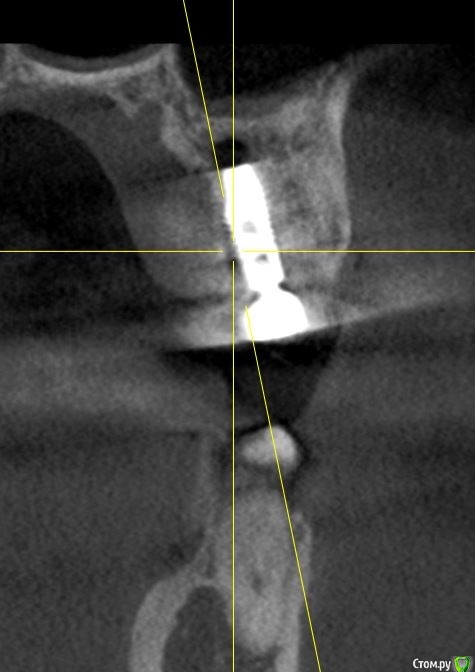

Irouil Опубликовано 29 сентября, 2020 Автор Поделиться Опубликовано 29 сентября, 2020 (изменено) По ориентации оси импланта на бугор антагониста я бы делал выводы о вестибулярном завале Не замерял сколько между ними, ну на глаз где-то 3 и есть Фото с винтами во рту нет, к сожалению, но ортопед рот тоже не смотрел, вердикт по снимкам Изменено 29 сентября, 2020 пользователем Irouil Ссылка на комментарий

Irouil Опубликовано 29 сентября, 2020 Автор Поделиться Опубликовано 29 сентября, 2020 Если включать перфекциониста, то есть незначительный завал, но это ж все нормально ортопедируется.Тут надо делить теорию и практику, на мой взгляд. Перкпучивать в человеке винты потому, что врач не хочет выключать перфекциониста - это не медицина, а IT или инженерия. С точки зрения практики А если говорить теоретически, то просмотрите на первый и последний предоставленные срезы: от зубов до винтов и между винтами минимально необходимые расстояния (замечу, что работа без шаблона), они между собой параллельны. Сдвигать корпусно 1.5 некуда - там вестибуло-медиальный корень 1.6 вестибулярно и дистально, а если убирать вестибулярный наклон - платформа выведет за пределы небной кортикалки. Если же двигать его корпусно вестибуло-медиально (чтобы не приближаясь к корню освободить пространство для небной ротации), то абсолютно идентичное движение должен совершить 1.4 - ровно в сторону корня 1.3. Получается, что единственное, что можно было бы подправить ТЕОРЕТИЧЕСКИ - немного сгладить медиальный наклон, но, опять таки, рискуя либо сближением с корнем 1.6 в пришеечной области, либо, что ещё хуже на мой взгляд, сближением с корнем депульпированного 1.3 в апикальной части. Так что это ещё тот вопрос - где и кто включает перфекциониста. На мой взгляд Ссылка на комментарий

Асхат Опубликовано 30 сентября, 2020 Поделиться Опубликовано 30 сентября, 2020 Может ортопед собрался винтовую фиксацию делать , в таком случае шахты могут выходить на щечный бугор. Как там расстояние до антогонистов ? Ссылка на комментарий

Irouil Опубликовано 30 сентября, 2020 Автор Поделиться Опубликовано 30 сентября, 2020 (изменено) Может ортопед собрался винтовую фиксацию делать , в таком случае шахты могут выходить на щечный бугор. Как там расстояние до антогонистов ?Миллиметров 7-8 от платформы до бугра будет, собственно по фдм на 1.5 видно - сам он 4 мм + недокручен 1-1.5 мм + по высоте 1.6 рядом стоящего еще пару мм Понятное дело, что ортопед хочет клеить в лаборатории. Но тут 1) до осмотра полости рта мало что можно сказать, если судить по этим снимкам, выходит все в пределах жевательной поверхности и 2) неужели ради этого удалять винты? Одна из классических позиций, определяющяя отношение врача к пациенту, звучит так - лечи как свою маму. Стали бы из-за выхода шахты на бугор переставлять маме винты? Изменено 30 сентября, 2020 пользователем Irouil Ссылка на комментарий

Irouil Опубликовано 30 сентября, 2020 Автор Поделиться Опубликовано 30 сентября, 2020 А как он обосновал что нужно убирать винты? Слишком небно импланты, слишком сильный медиальный завал, слишком близко зубы Ссылка на комментарий

shy Опубликовано 30 сентября, 2020 Поделиться Опубликовано 30 сентября, 2020 коллеги , подскажите пожалуйста , что не так с ангуляцией? я просто совсем далек от ортопедии , но тут же градусов 6-10, при 15-20 + градусах делают цементную , насколько я знаю. 1 Ссылка на комментарий

Fin Опубликовано 30 сентября, 2020 Поделиться Опубликовано 30 сентября, 2020 (изменено) Слишком небно импланты, слишком сильный медиальный завал, слишком близко зубыВидимо док слишком замороченный в плане позиционированния. Решать по КТ конечно не правильно, посмотреть бы. Думаю доку прийдётся поработать с десной немного, а так можно и цементную и винтовую фиксацию реализовать. Да и тут не особо понятно, если вы при перестановке отступите от зубов подальше до между иплантами расстояния совсем не будет. С таким отношением коллеги Вы сами скоро слепки начнете снимать)) коллеги , подскажите пожалуйста , что не так с ангуляцией? я просто совсем далек от ортопедии , но тут же градусов 6-10, при 15-20 + градусах делают цементную , насколько я знаю.Поидее винтовая фиксация должна быть при условии что шахта не будет выходить на бугры или вестибулярно, иначе прийдётся пожертвовать эстетикой или бугром. Мультиюниты могут помочь сделать винтовую при больших углах (но не единичные коронки) или же шаровидная отвертка.Недавно на 15° абатменте делал винтовую виксацию при помощи шаровидной отвёртки, проблем не было. Изменено 30 сентября, 2020 пользователем Fin Ссылка на комментарий